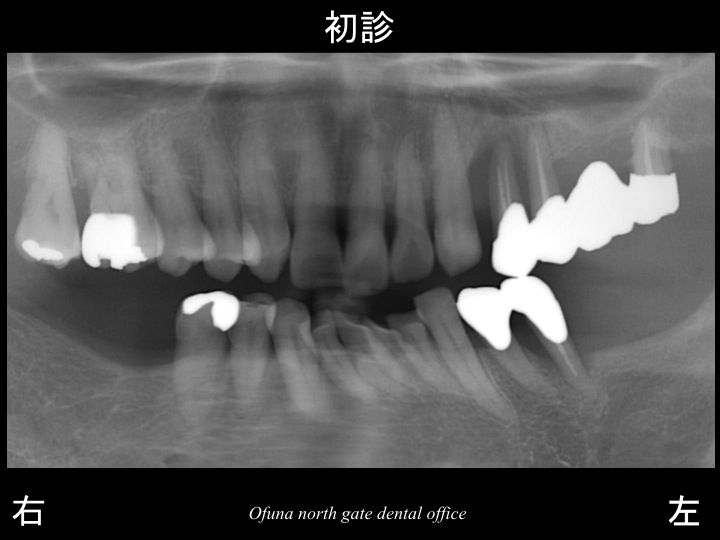

以下が初診時です。

上顎左側の奥歯が「グラグラする」とのことで来院されました。

この患者様は、すでに多くの歯が欠損しています。

欠損している部位が多いとその部位では噛めませんので、

必ず他の歯に噛む力の負担が加わってしまいます。

本日の最初に書きましたように

歯が欠損している状態を放置してはいけません。